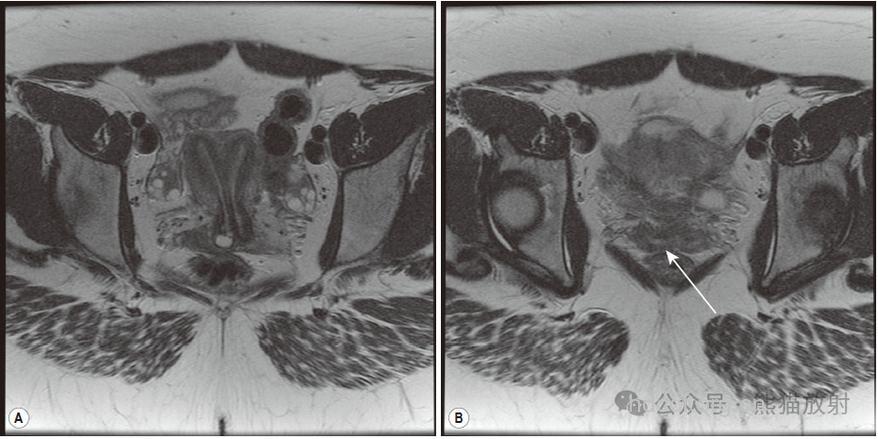

小雨,今年25岁,曾经怀孕过两次,但是到最后都流产了。在检查时发现,小雨有两个阴道、两个宫颈、两个子宫(又称完全纵隔子宫)。据悉,这属于典型的生殖道畸形案例。

近日,广州仁爱医院已收治了这个在临床医学上非常罕见的患者。主诊医生已为小雨施行了宫腔镜下的生殖道矫正术,双阴道、双宫颈、双子宫矫正为正常的生殖道。目前,小雨恢复良好。双子宫、双阴道、双宫颈惹祸,导致流产 小雨婚后不久曾经怀孕,但是不久就流产了。2008年12月,因为再次怀孕到广州仁爱医院妇科医生王秀芹主任求诊。当时经B超检查显示,小雨是双阴道、双宫颈、双子宫。鉴于双子宫不利于胎儿生长,很可能导致流产。由于各方面的原因,小雨当时并没有治疗。出于生育的考虑,直到2009年8月19日,小雨才到广州仁爱医院要求治疗。 据王秀芹主任介绍,小雨的双阴道、双宫颈、双子宫是先天性疾病,原因不明。这可能与环境、遗传等因素有关。这种情况会造成习惯性流产、早产、胎位不正、死胎等严重后果。目前医院已经为小雨施行了宫腔镜下的生殖道矫正术,恢复良好。痊愈后,小雨可以正常孕育孩子,过正常的生活。生殖道畸形案例层出不穷 类似小雨这种先天性生殖道畸形并不少见。据不完全统计,近两年来,广州仁爱医院已经收治了近50例生殖道畸形的患者,最常见的是先天性阴道闭锁(俗称石女),其中最罕见的案例是来自四川的“双阴道四肾女孩”、世界最罕见石女——患者为先天性无阴道、无子宫,盆腔孤立肾,单侧卵巢,全国估计不超过十人。这两个案例曾引起多家媒体的关注报道。 据悉,生殖道畸形常见的有先天性阴道闭锁、子宫畸形、无阴道等情况,多是患者在常规体检、无法顺利过夫妻生活、进行流产手术时才发现生殖道畸形的情况。生殖道畸形的情况经过微创手术矫正,一般可以恢复正常。 如何孕育健康的宝宝? 1、要认真对待婚前医学检查,通过检查发现的一些疾病,如乙肝、性病等,这些疾病只有治愈后才能怀孕。 2、怀孕后立即建立围产保健卡,定期检查,14-20周时可做唐氏筛查,28周前做B超检测等,这些检查都可以在怀孕早期查出胎儿是否畸形。 3、防止生殖道感染性疾病。孕妇发现自己分泌物有异常的也要及时就医,不能因为怀孕而拒绝用药甚至讳疾忌医。